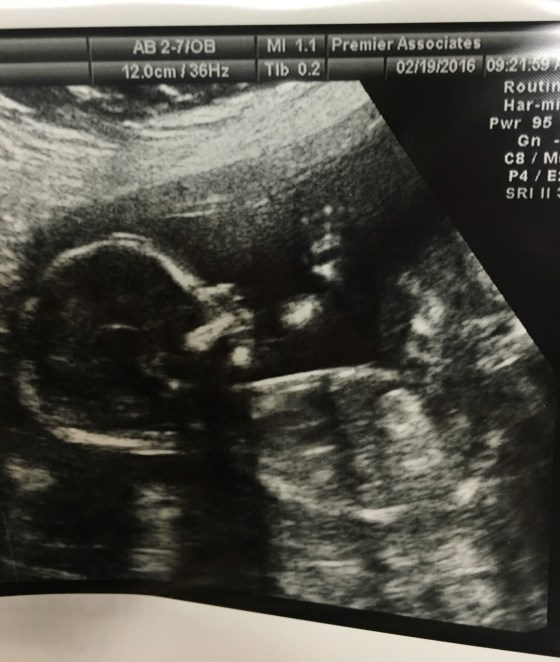

I went to a specialist this week for what I thought was a preeclampsia consultation. I was a little surprised that they wanted to do an ultrasound since I had just had one the week before. This was a Level 2 machine so the ultrasound pictures were very clear.

To me it looks like the baby is smiling and waving hiiii!

I feel like that looks like Gracie’s face.

I was all very excited after this sonogram, texting the pictures to everyone I knew. Then quickly things changed. They sat me down with a genetic counselor to tell me the ultrasound showed a soft marker for Trisonomy 21. It’s called an Echogenic Bowel. Instantly I was crying. My husband stayed home with the kids because we thought this was going to be a very basic appointment so I was all alone.